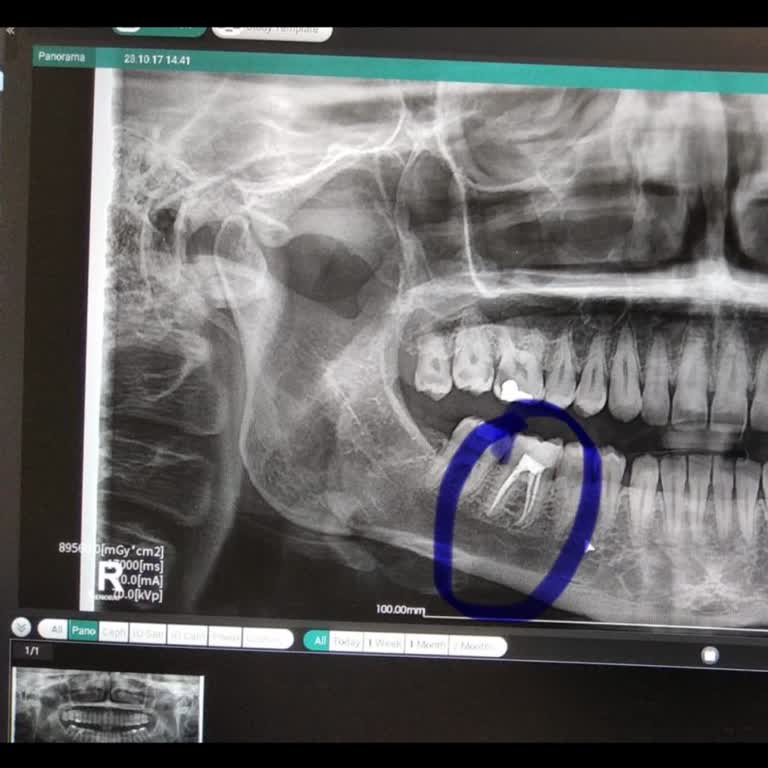

2022 Kasım ayında kanal tedavisi için Dentomega Diş Kliniği diş hekimi h** Ş*e gittim. Kanal tedavisi diye başlanıp kanal tedavisi yapılmadı ve üstüne kanal tedavisinde kullanılan bir aletin ucunu dişimde unuttular. Tedavim tamamlanmadı üstüne büyük bir hata yapıldı. O tarihlerde manipüle edildim. H...